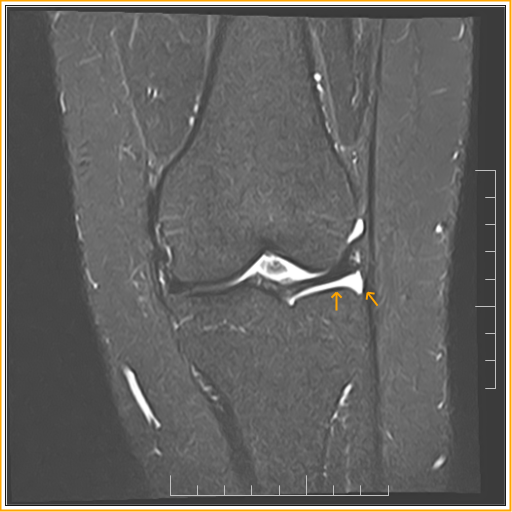

Floating MeniscusMRI Radiology Imaging Floating Bone In My Knee These fragments can float freely in the joint space and synovial fluid, but they can also become trapped in the knee, causing pain and inflammation. you may feel something floating in your knee joint because loose pieces of cartilage could be in there. When these fragments get trapped between the. a loose body in the knee is a. Floating Bone In My Knee.